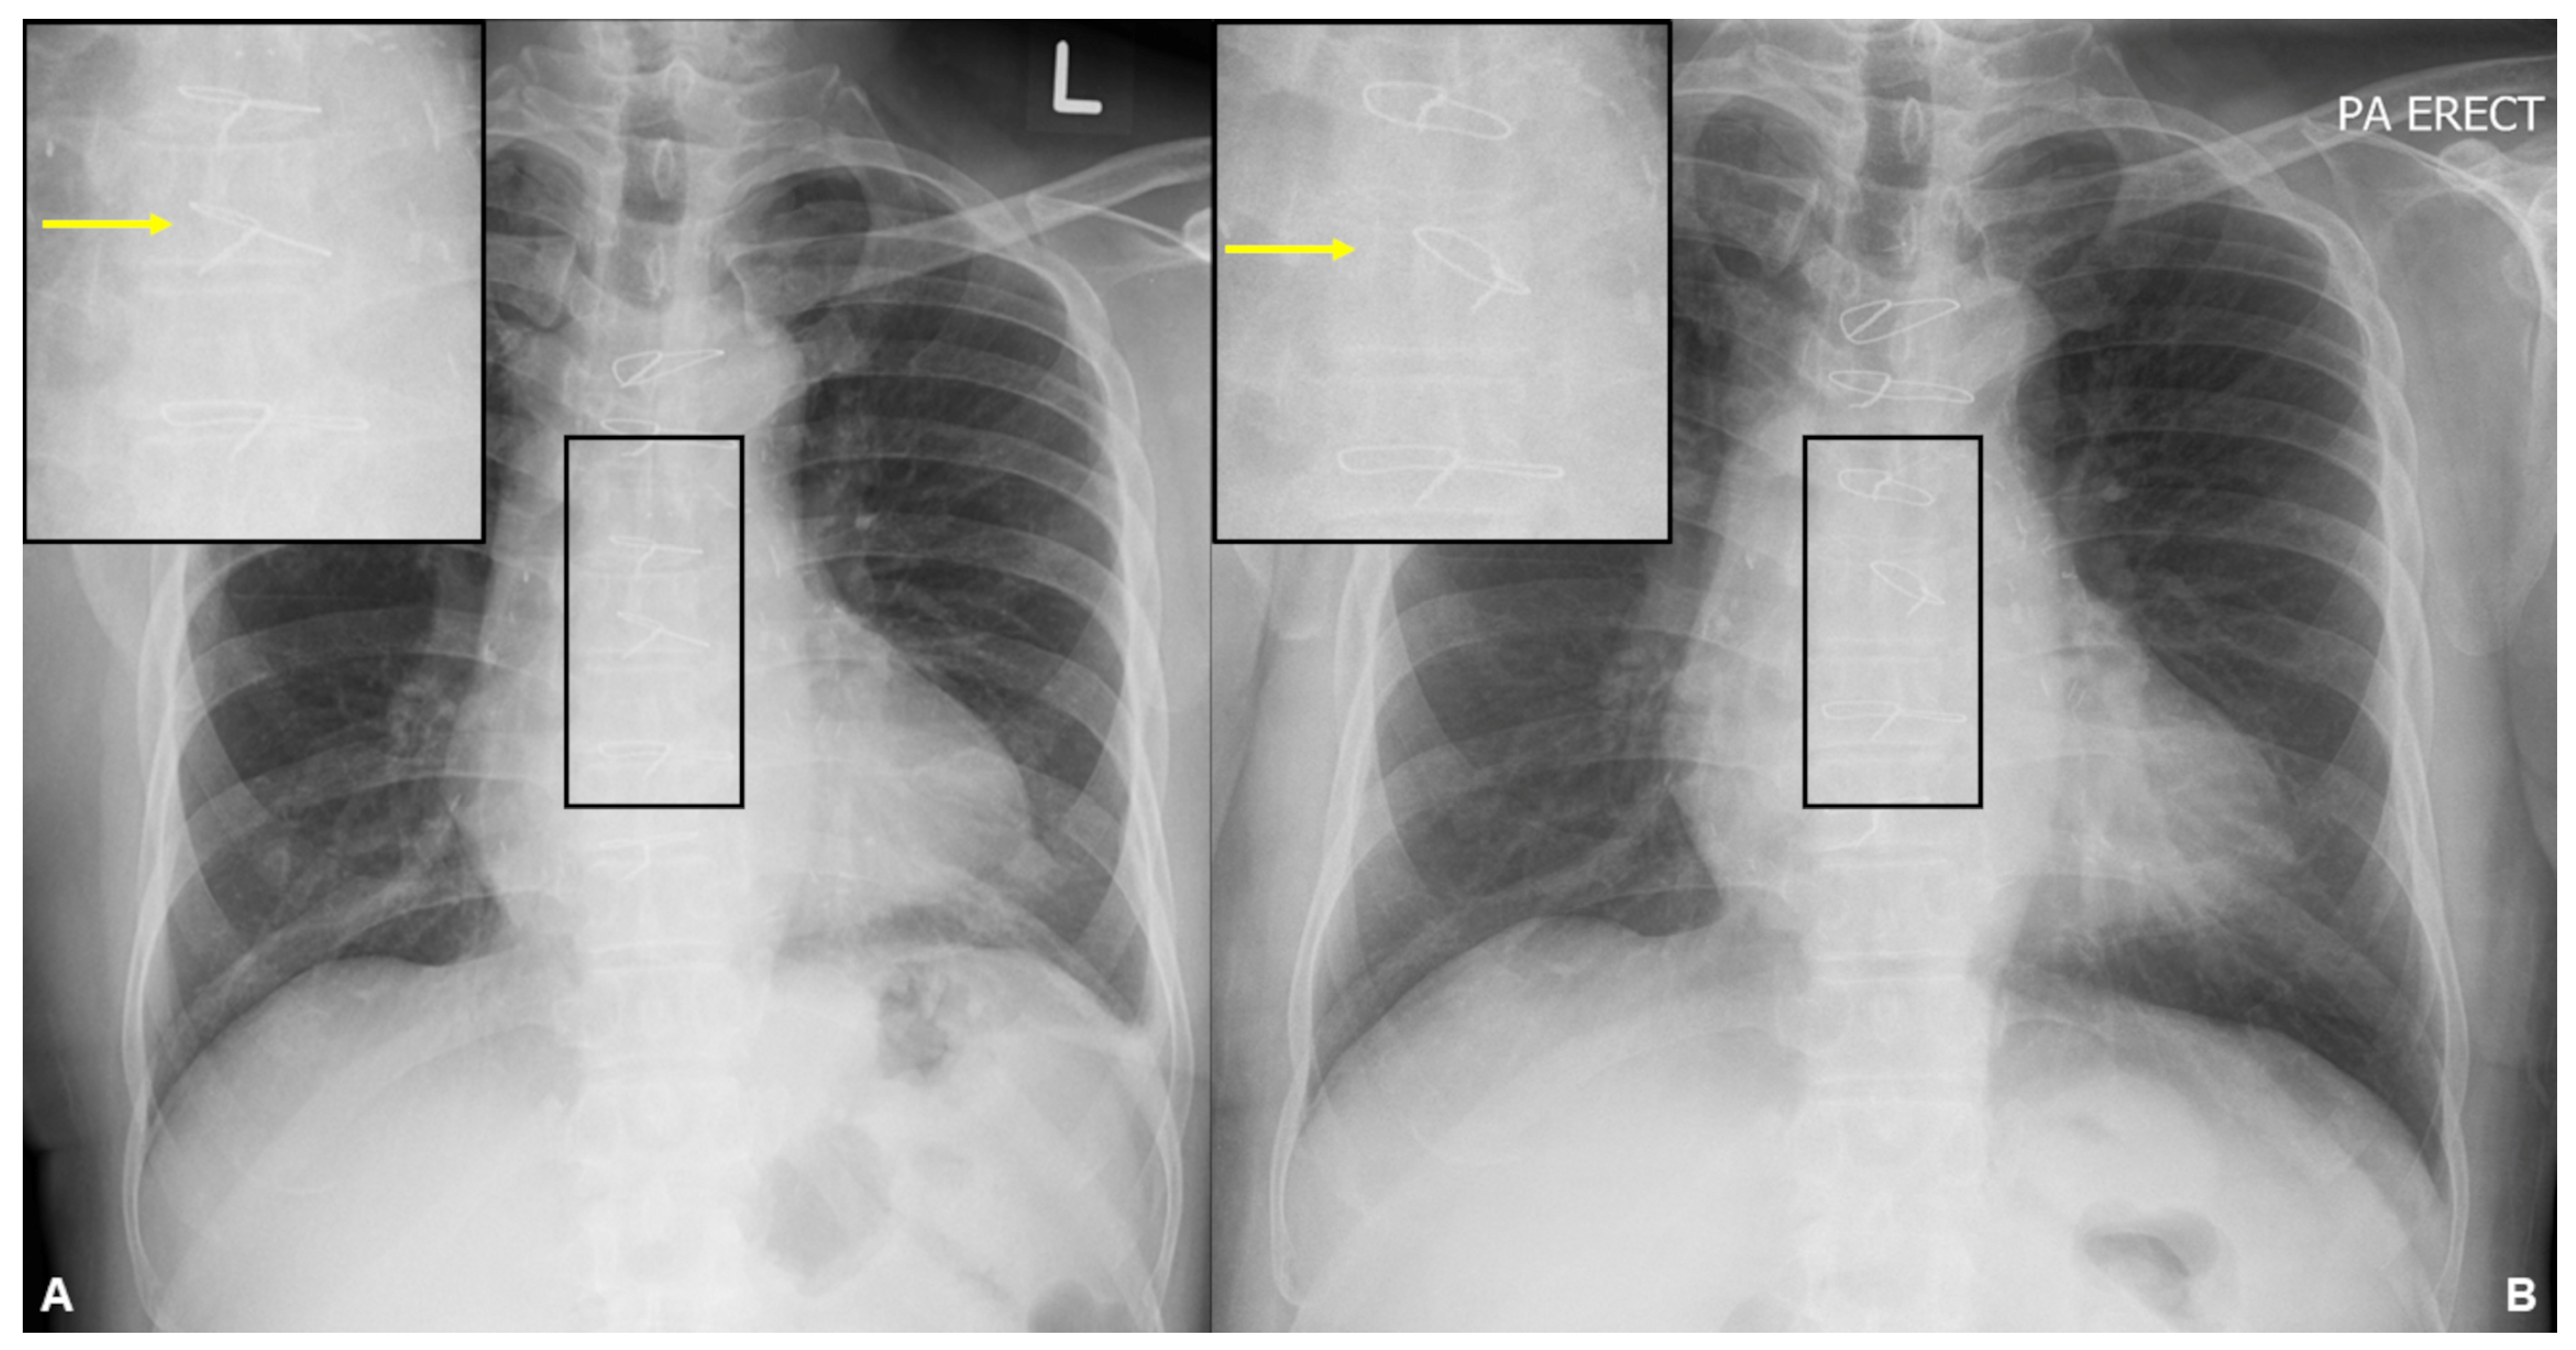

A frontal chest radiograph was obtained on presentation (B), showing left lateral displacement of a sternal wire in a chest radiograph from 3 years ago (A). No fracture of the sternal wires is seen. Initial laboratory investigations showed a low haemoglobin level of 8.8 g/dL. The platelet and white cell counts were within normal limits. The serum creatinine level was elevated (149 µmol/L; estimated glomerular filtration rate of 42 mL/min) with normal serum calcium and electrolyte levels. The liver function tests were normal, and the serum alkaline phosphatase (ALP) and lactate dehydrogenase (LDH) levels were not elevated.